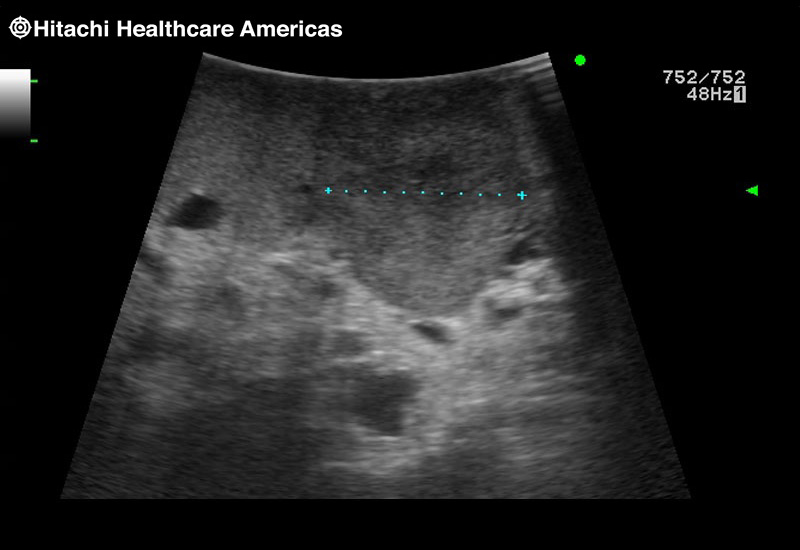

Superior guidance for all applications

Fujifilm Healthcare Americas is committed to designing tools that help surgeons navigate inside the human body and provide the necessary information to immediately make critical surgical decisions.

Fujifilm Healthcare's dedication to Surgeons provides outstanding ultrasound technology, professional support and the specialized tools necessary to best perform comprehensive real-time ultrasound imaging in Breast Surgery, General Surgery, Laparoscopic Surgery, Neurosurgery, Robotic Surgery and Surgical Oncology.

Recognized for our outstanding image quality, outstanding system reliability and intuitive use of cutting edge technology, Fujifilm Healthcare remains the standard in the field of Surgery.

Recognized for our outstanding image quality, outstanding system reliability and intuitive use of cutting edge technology, Fujifilm Healthcare remains the standard in the field of Surgery.